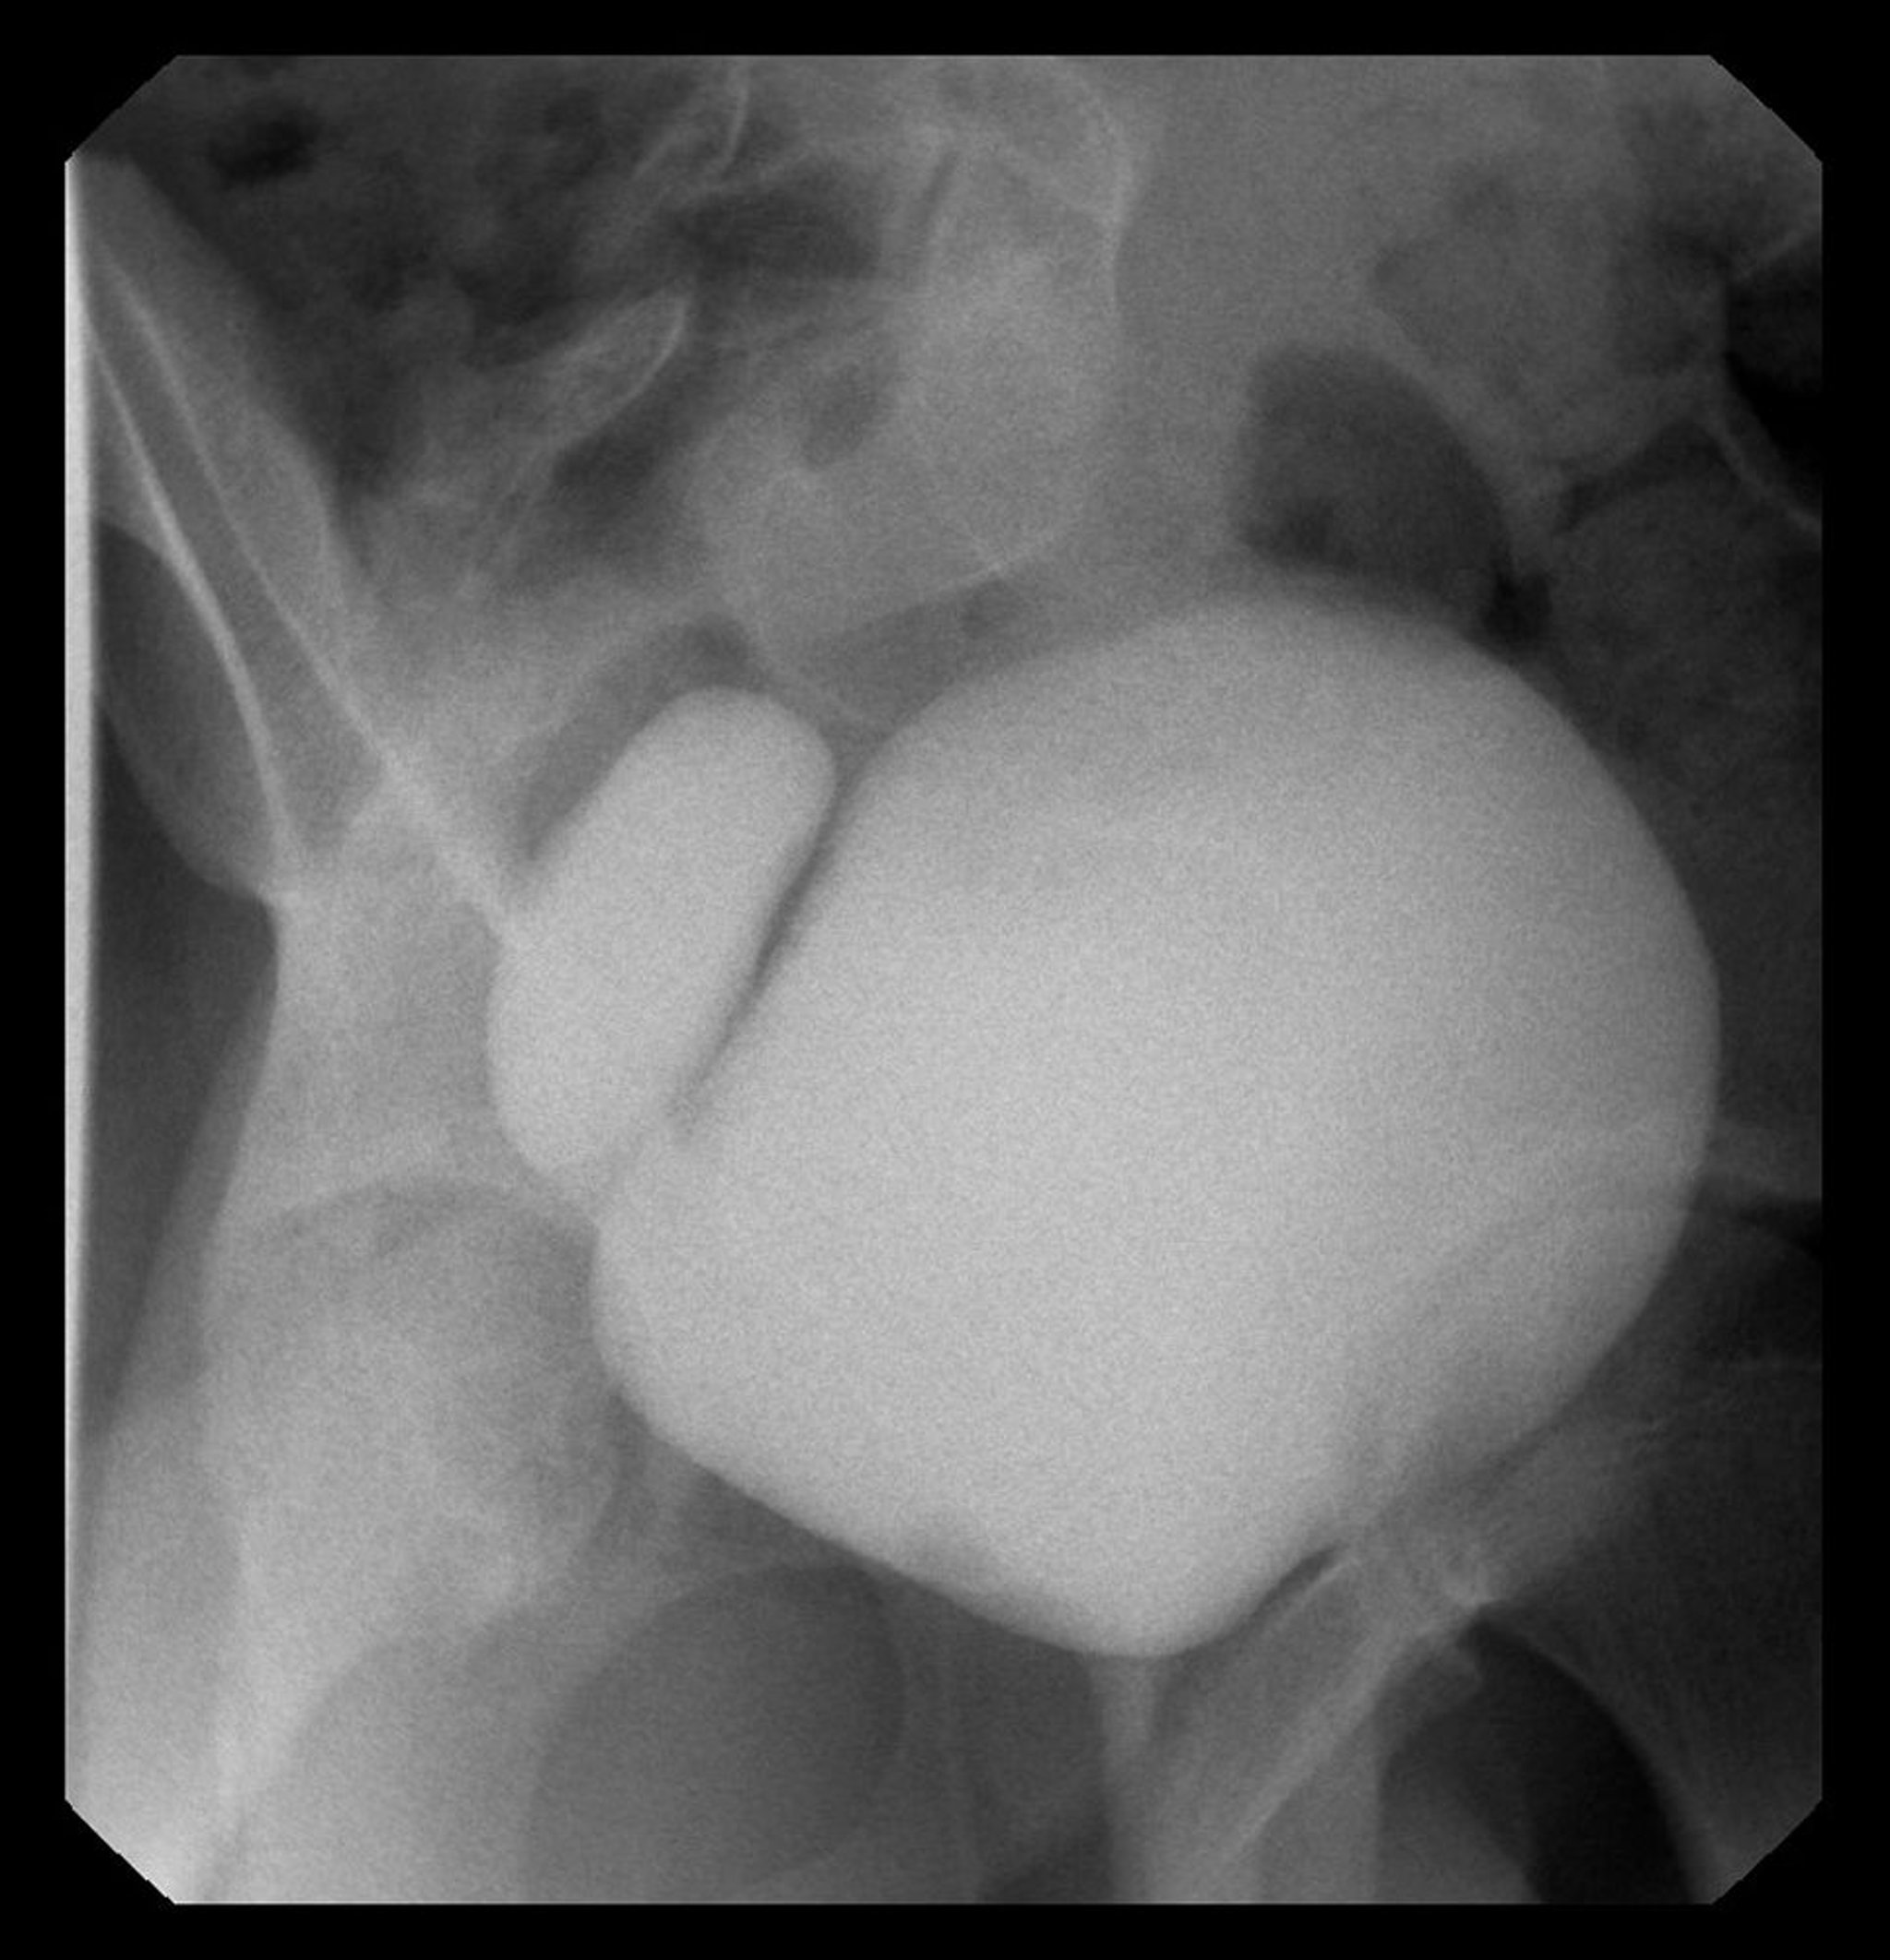

Essa imagem mostra cistograma com divertículo vesical do lado direito.

Imagem cedida por cortesia dos Drs. Ronald Rabinowitz e Jimena Cubillos.